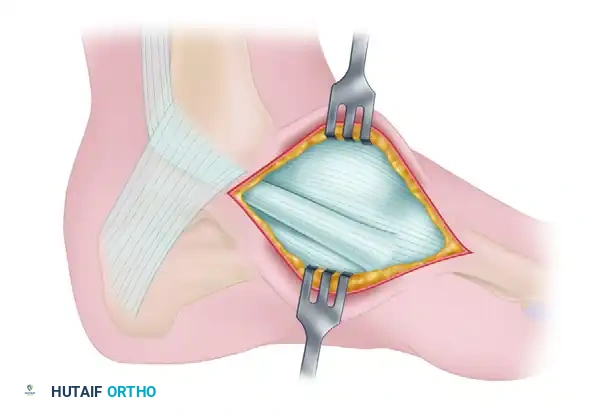

Deepen the dissection through the subcutaneous tissue, taking care to protect the medial dorsal cutaneous nerve. Incise the sheath of the posterior tibial tendon longitudinally. Reflect the tendon to expose the underlying accessory navicular and its synchondrosis with the main body of the navicular.

Figure 82-39B: Exposure of the posterior tibial tendon and the accessory navicular.